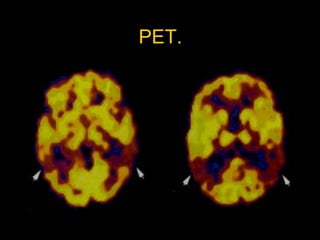

Disminución de la recaptura de 18-fluorodopa PET en putamen post. E. Parkinson, comparado con un control normal. Tomado de: An algorithm /decisión tree for the management of Parkinson’s disease (2001):  Treatment guidelines.  CW Olanow, RL Watts, WK Koller editors. Neurology 2001;56(11) suppl 5:S3.

Estudios complementarios. TAC, EEG y SPECT: poco útiles.  PET 18F-dopa o SPECT   -carbometoxi-3-  -(4-iodofenil) tropano. Captación disminuida en estriado (putamen post).  Parkinson plus: disminuida en putamen + N. caudado.  Parkinson plus: disminución receptores D2 postsinápticos utilizando ligandos como raclopride en PET  E. Parkinson idiopática: nls).  Perfil bioquímico en jóvenes: enf. Wilson.  Neuropatología: “Standard oro”.

Genética. Mutaciones en familias.  Mutación  en gen de la   sinucleina (SNCA), en Cr 4q. denominado PARK 1.  Mutuación puntual G209A: alanina por treonina en la posición 53 ( Ala53Thr). Mutación Ala30Pro.  Mutaciones Ala53Thr y Ala30Pro.  Disminución recaptura de 18F-dopa en el estriado (putamen) en PET.  Filamentos de   -sinucleína en cpos Lewy.  Sin embargo las mutaciones en la   -sinucleina: causa rara de E. Parkinson.  Persina:   y   sinucleina.

Genética. Mutaciones enfamilias. Mutación en gen de la  sinucleina (SNCA), en Cr 4q. denominado PARK 1. Mutuación puntual G209A: alanina por treonina en la posición 53 ( Ala53Thr). Mutación Ala30Pro. Mutaciones Ala53Thr y Ala30Pro. Disminución recaptura de 18F-dopa en el estriado (putamen) en PET. Filamentos de  -sinucleína en cpos Lewy. Sin embargo las mutaciones en la  -sinucleina: causa rara de E. Parkinson. Persina:  y  sinucleina.